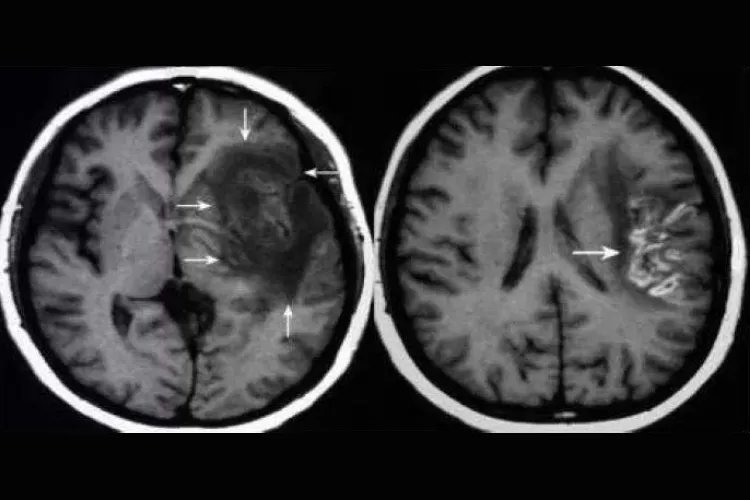

新型隐球菌脑膜脑炎CT可见脑实质(多发生于基底节区)出现斑点状低密度灶及脑膜增厚、强化。

结核性脑膜脑炎患者CT可见病灶密度增高,后期局部可见点状钙化,若肉芽肿形成则见局部脑池闭塞,增强扫描出现脑膜线样强化和(或)结节状强化形态不规则。